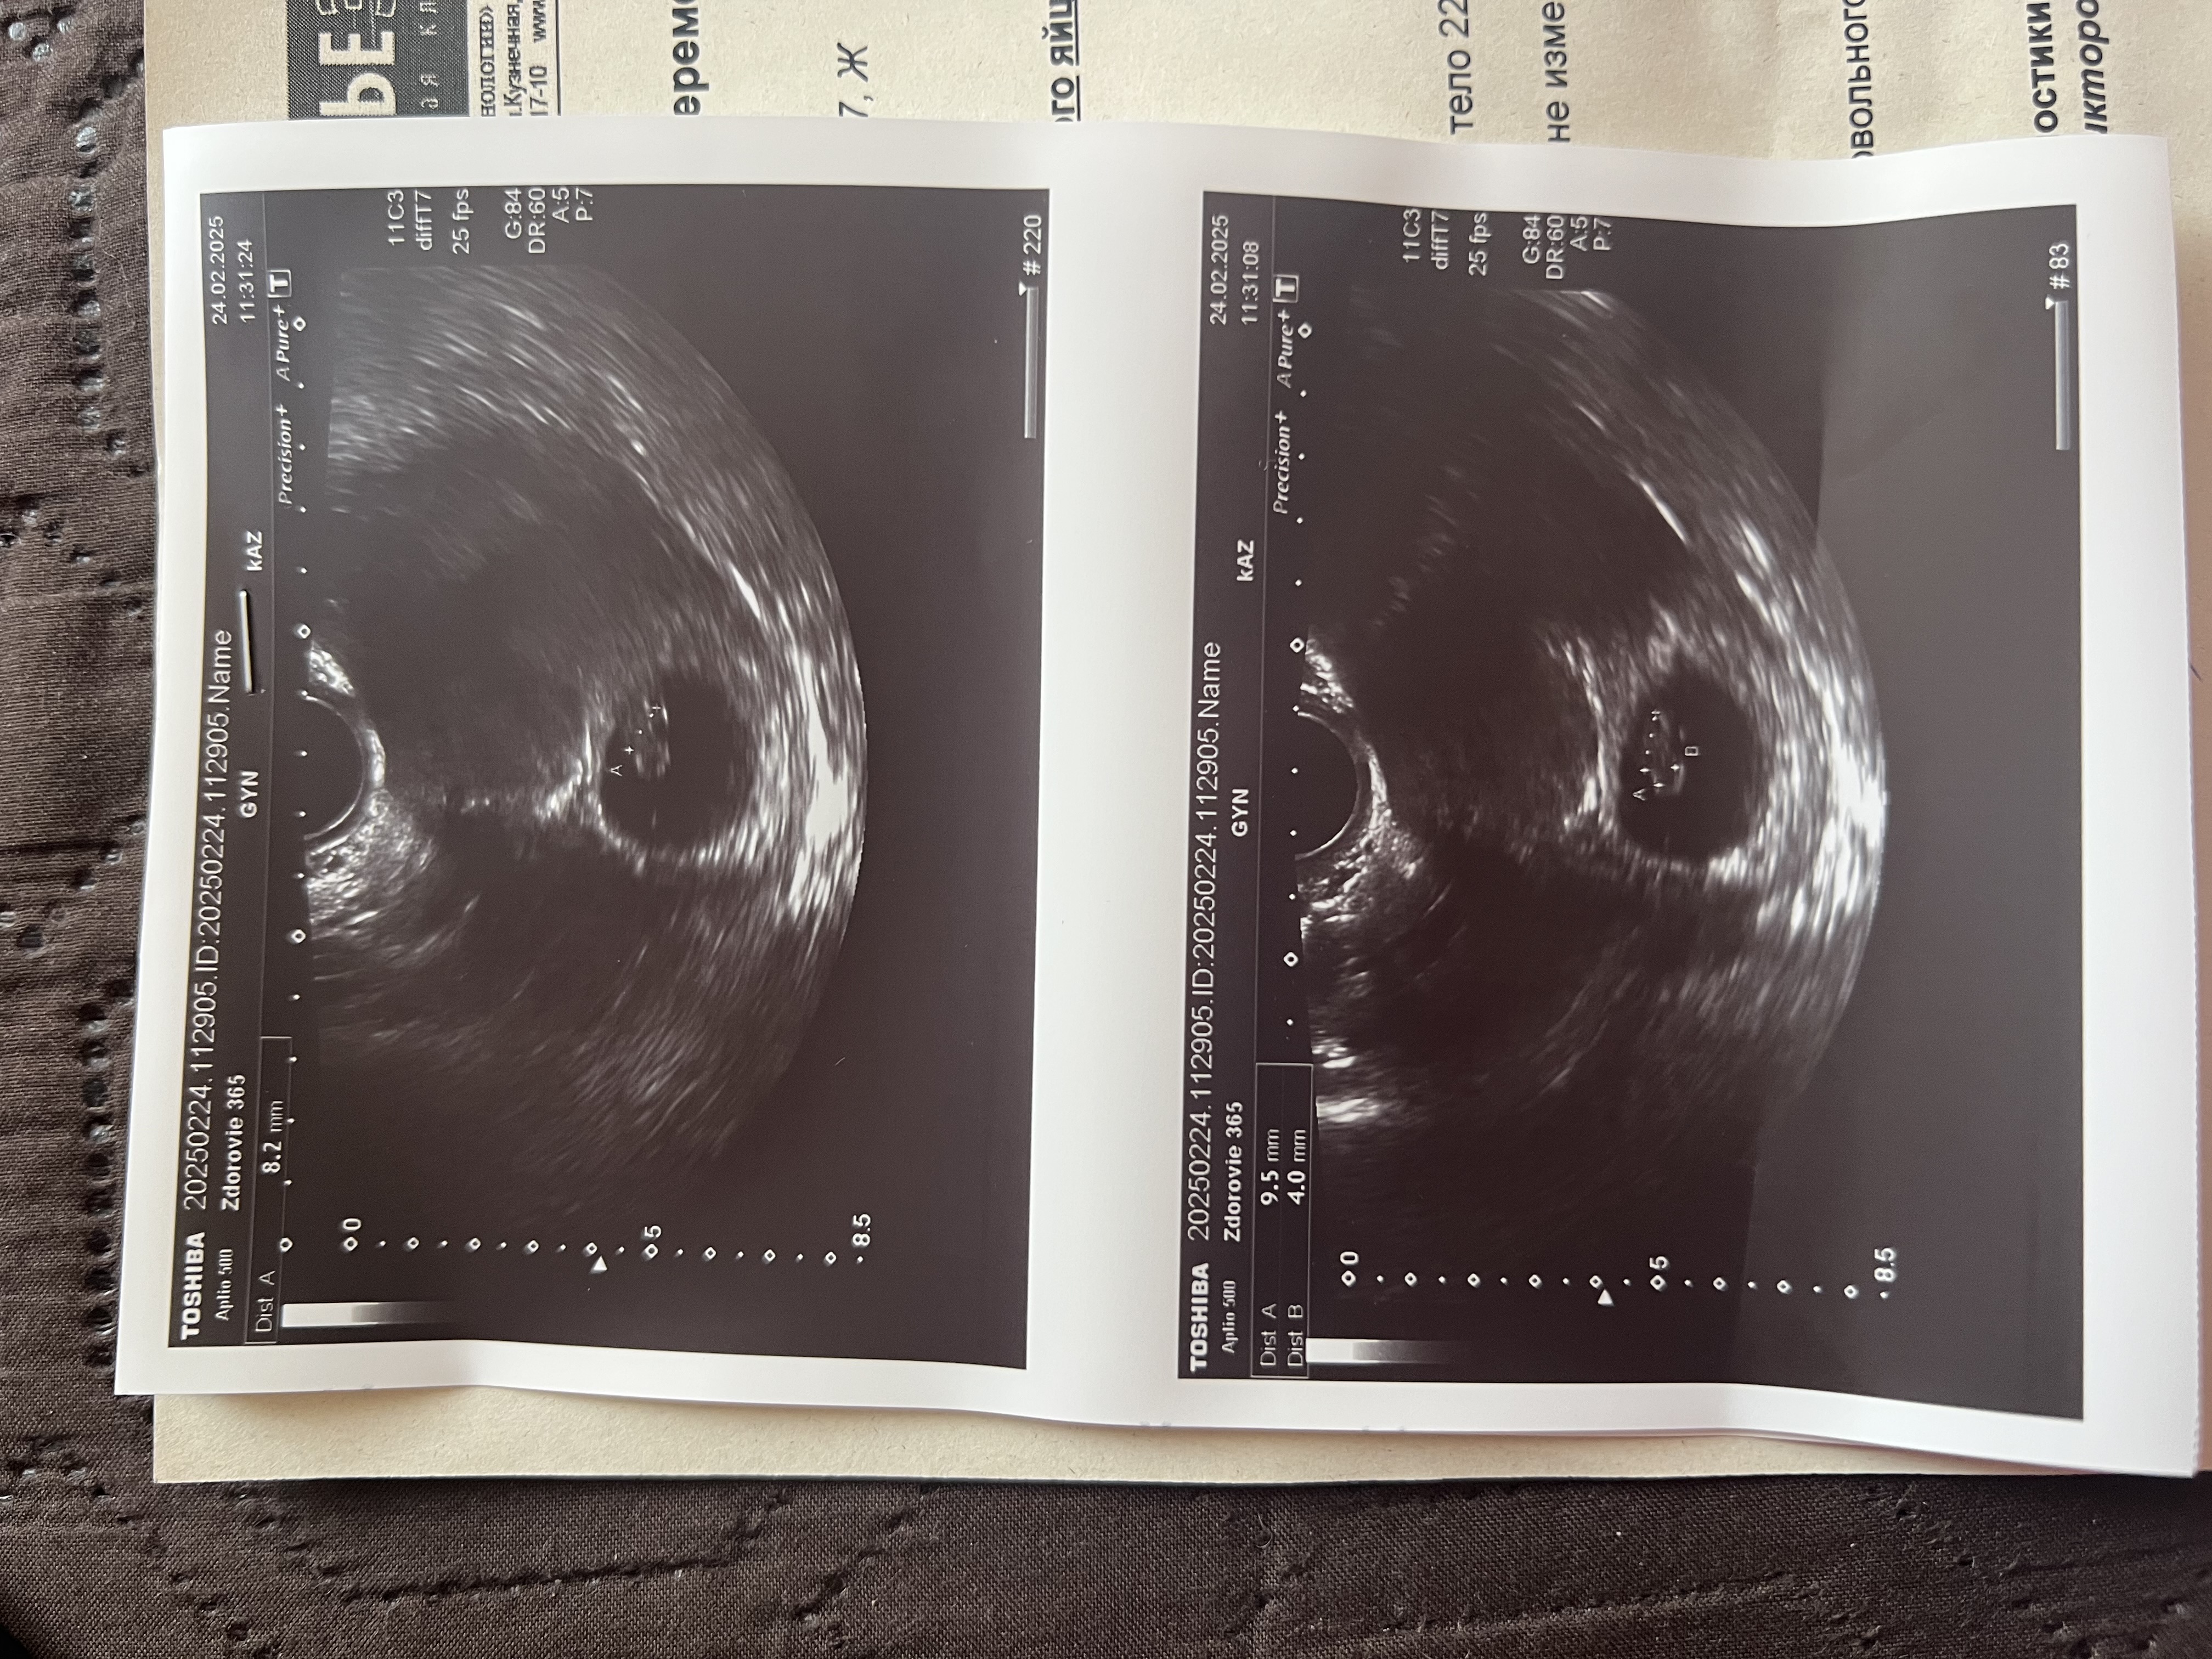

Изображение тоже очень интересно, знаю, у многих совпадает, хотя понятно, что тут вероятность угадать 50/50. Вот не могу понять кто тут и всё, УЗИ в 7 недель

Какая интересная тема, а если 10 недель то можно так посмотреть или уже поздно, УЗИ вагинально, кто подскажет? Изображение